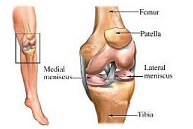

La articulación de la rodilla está formada por las partes inferior del fémur, superior de la tibia y posterior de la rótula actuando como una gran bisagra. Es la articulación más lesionada en el deportista y su tratamiento exige un gran conocimiento de la anatomía así como de la cirugía traumatológica, protésica y artroscópica.

Lesiones ligamentosas de rodilla

Las lesiones ligamentosas de la rodilla tienen lugar fundamentalmente en la práctica deportiva aunque también pueden aparecer, y por ello deben descartarse, en el contexto de un politraumatismo. Obedecen generalmente a mecanismos de torsión y/o desviación femoral con la tibia fija en el suelo dando lugar a la rotura. Los deportes habituales de este tipo de lesiones son: futbol, esquí, baloncesto, voleibol, balonmano, artes marciales, deportes de raqueta, patinaje y rugby. Es realmente difícil la exploración clínica tras el traumatismo inicial debido a la inflamación y dolor en la rodilla por lo que en ocasiones una sedación anestésica puede ser de gran ayuda a tal efecto. Finalmente las técnicas de imagen y el estudio artroscópico completarán el estudio diagnóstico. El tratamiento de las lesiones ligamentosas de rodilla depende de diversos factores como la edad del paciente y el tipo de estructuras implicadas en la lesión. Generalmente, aquellas lesiones que producen inestabilidad o bloqueo de la rodilla reciben tratamiento artroscópico y rehabilitación posterior para recuperar la función normal de la rodilla.